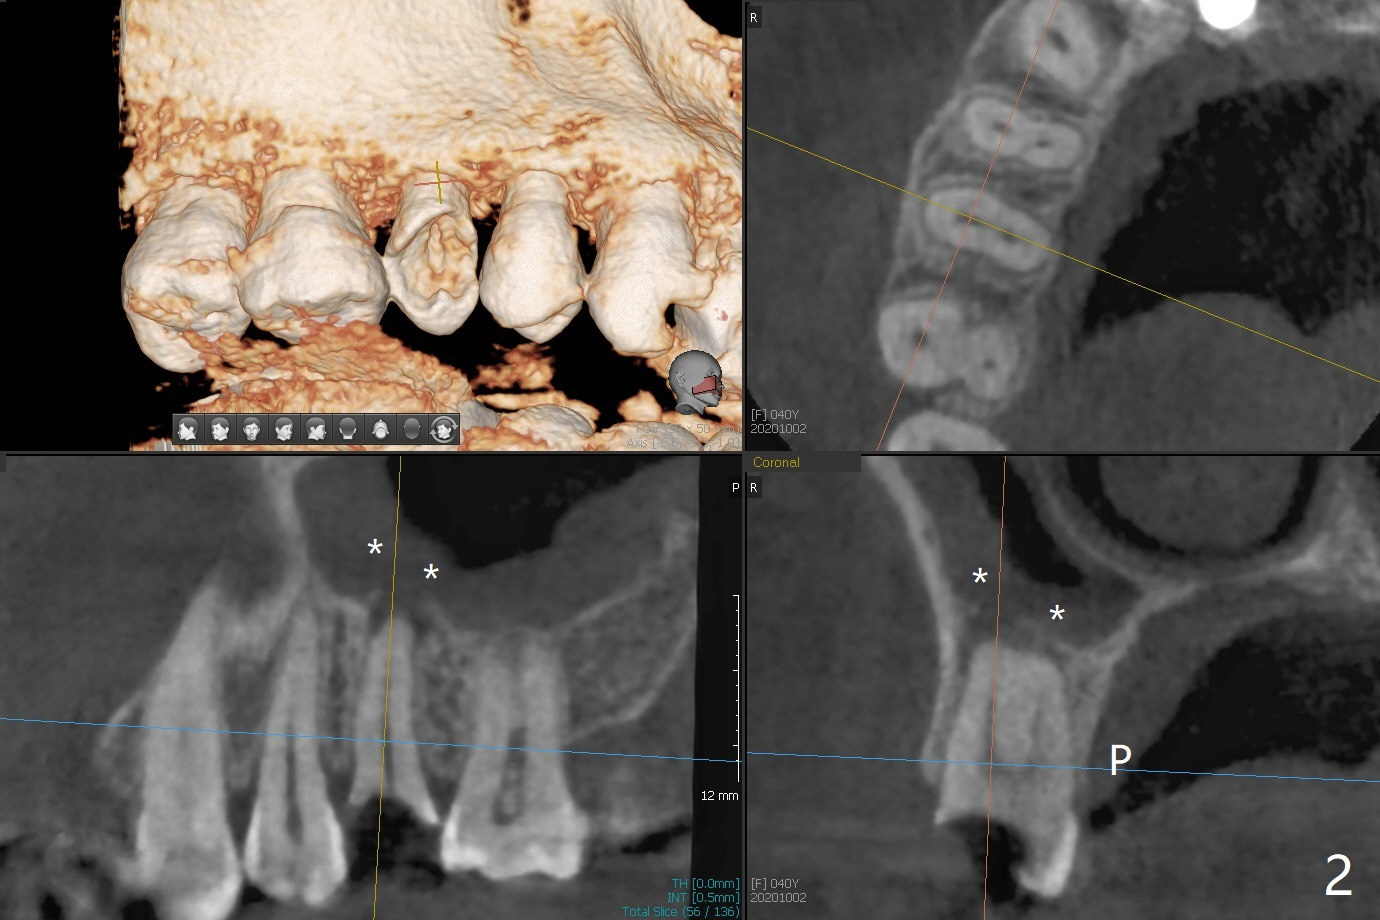

40岁女右上5树脂脱落,少许龋齿,近中边缘稍微龈下(图一:^),轻微叩痛(*)。经过商讨,她选择拔除植牙。CT检查显示上颌窦膜增厚(图二:*),为了减少术后上颌窦炎,第一,Z Pack(上呼吸道广谱抗菌素)和Medrol Dose Pack(激素)处方已开;第二,拔牙后(图三),将PRF膜推入上颌窦(图四:橘黄色),然后粘性骨块(红色圆圈);第三,植体长度刚好穿过窦底板(图五:11.5毫米)。Return to No Deviation 手术 No Neighboring Caries No Antibiotic 8, 10,30/31,19 Armaments 提升 Xin Wei, DDS, PhD, MS 1st edition 10/02/2020, last revision 03/28/2021